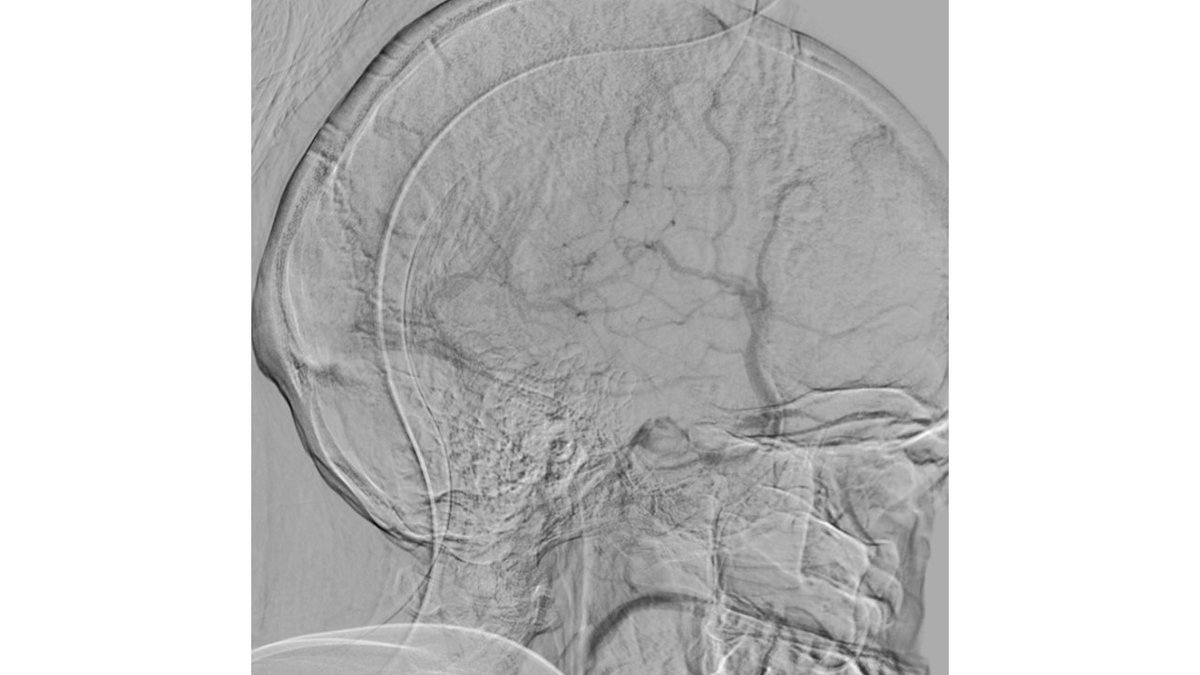

MRV shows left Transverse and sigmoid sinus thrombosis. No improvement after 2 days of IV heparin. Pt requires heavy sedation, ventilation for headache/agitation.

DSA also confirmed the extensive clot. In view of her recent LSCS 20 days ago, we were hesitant about giving IV lytics (urokinase infusion). Hence went in with an ACE 5 Max catheter and sucked out a mountain of clot